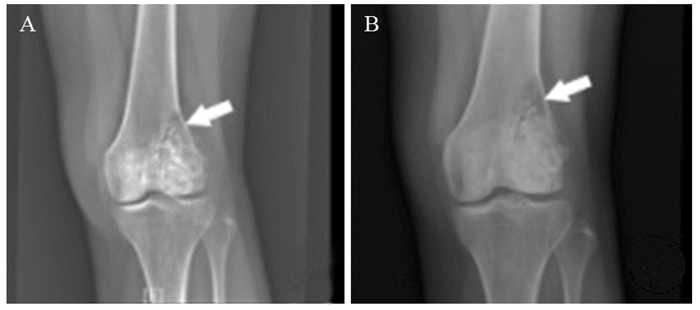

方法回顾性分析获得随访的451例骨巨细胞瘤患者发病部位、手术方式、Campanacci分级、病理性骨折、肺转移与骨巨细胞瘤复发率的相关性。

结果脊柱骨盆骨巨细胞瘤的复发率较膝关节周围(P < 0.001)、桡骨远端(P=0.005)及其他部位(P < 0.001)骨巨细胞瘤复发率高;Ⅲ级骨巨细胞瘤单纯刮除术后复发率高于扩大刮除术(P < 0.001)以及瘤段或分块切除术(P=0.002),差异有统计学意义;行单纯刮除术的CampanacciⅠ级、Ⅱ级、Ⅲ级骨巨细胞瘤术后复发率比较差异有统计学意义(P=0.028),行扩大刮除及瘤段或分块切除术后的CampanacciⅡ级与Ⅲ级的骨巨细胞瘤复发率比较差异无统计学意义(P > 0.05);骨巨细胞瘤复发病例肺转移率高于无复发病例肺转移率,差异有统计学意义(P < 0.001);伴病理性骨折与无病理性骨折骨巨细胞瘤术后复发率比较差异无统计学意义(P > 0.05)。

结论手术方式影响骨巨细胞瘤的肿瘤外科边界,与术后复发率密切相关;复发病例的肺转移率明显升高;为改善骨巨细胞瘤患者预后,临床上骨巨细胞瘤手术应考虑足够的外科边界。

Abstract:ObjectiveTo investigate the relationship between the characteristics and postoperative recurrence of giant cell tumor (GCT) of bone.

MethodsA total of 451 patients followed up with GCT of bone undergoing surgical treatment were reviewed to analyze the association of the characteristics, including tumor location, operation method, Campanacci grade, pathological fracture and pulmonary metastasis, with the recurrence rate of GCT bone.

ResultsThe recurrence rate of GCT in the spine or pelvis was significantly higher than that around the knee (P < 0.001), in distal radius (P=0.005) and in other parts (P < 0.001). The recurrence rate of grade Ⅲ GCT after simple excochleation was significantly higher than that after enlarged excochleation (P < 0.001) and tumor segment or block resection (P=0.002). The recurrence rate of GCT undergoing simple excochleation among cases of Campanacci gradeⅠ, Ⅱ and Ⅲ was significantly different (P=0.028); however, for GCT undergoing enlarged excochleation and tumor segment or block resection, there was no statistically significant difference of the recurrence rate between cases of gradeⅡ and Ⅲ (P > 0.05). The pulmonary metastasis rate in the recurrence cases of GCT was significantly higher than that in no recurrence cases (P < 0.001). There was no statistically significant difference of the recurrence rate of GCT between cases with and without pathological fracture (P > 0.05).

ConclusionThe surgical procedure affects the surgical boundary of GCT, which is closely related to the postoperative recurrence rate; the pulmonary metastasis rate of recurrent cases is significantly increased; adequate surgical boundaries for the surgical treatment of GCT may be essential to improve the prognosis of patients with GCT.